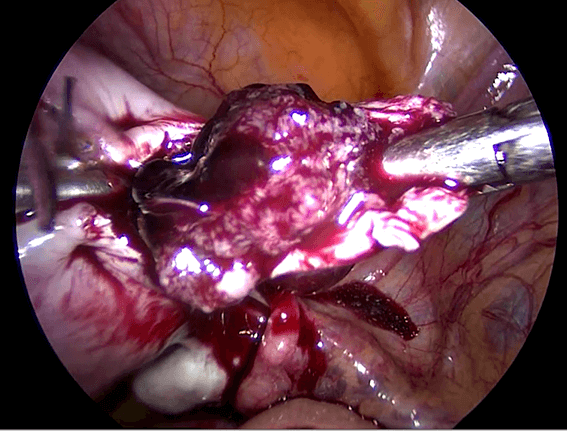

3) Eksisi laparoskopi kehamilan kornu

Saat kehamilan ektopik berada di daerah kornu rahim ( Gambar 7.4 ), maka kehamilan biasanya didiagnosis masih lama lagi. Kehamilan kornu jauh lebih sulit untuk dieksisi secara laparoskopi karena ukuranya lebih besar dan dapat berdarah dengan menyebar luas. Teknik ini melibatakan suntikan vasopressin disekitar kornu kehamilan ektopik dan penempatan jahitan purse string di sekitarnya. Kemudian sayatan dibuat untuk enukleasi kehamilan ektopik. kerusakan kemudian dijahit. Pada kehamilan kornu yang besar, bagian dari rahim harus diangkat bersama-sama dengan tuba. Pada kasus- kasus yang sulit, laparotomi mungkin diperlukan.

Reseksi laparoskopi kornu kehamilan ektopik

Pada tahun 2009 nyonya UDS datang mengunjungi saya , dia telah menikah 3 tahun dan dia tidak bisa hamil. Histerosalpingogram yang dilakukan di rumah sakit yang lain menunjukkan kedua tubanya tersumbat / terblokir. Dia menjalani laparoskopi , dan laparoskopi menunjukkan ukuran rahim yang normal. Kedua tuba nya normal dan dipatenkan setelah insulfasi tuba dilakukan dibawah tekanan. Dia hamil secara spontan 2 bulan setelah menjalani laparoskopi namun sayangnya kehamilan berakhir dengan aborsi yang terlewatkan. Dia telah menjalani evakuasi hasil konseptus. Pasca operasi , keadaan dia baik-baik saja akan tetapi tidak dapat hamil. Dia telah diberikan beberapa siklus klomifen sitrat namun tanpa membuahkan hasil. Pada tahun 2011, dia menjalani siklus inseminasi intrauterin setelah diberikan suntikan hormon perangsang folikel ( FSH ). Setelah prosedur dilakukan , dia hamil akan tetapi sayangnya kehamilan itu adalah kehamilan ektopik. Dia menjalani reseksi laparoskopi kornu kanan kehamilan ektopik di tahun 2011 ( Gambar 26.7 – 26.11 ) ( simak video 26.3 ). Pasca operasi di tahun 2013 dia menjalani histerosalpingografi dan menunjukkan bahwa tuba kiri tidak paten. Dia dapat hamil setelah menjalani IVF.

Pembahasan

Kornu kehamilan ektopik tidaklah umum. Biasanya didiagnosisnya terlambat karena pasien dengan kondisi seperti ini tidak memliki banyak gejala-gejala. Pecahnya kehamilan ektopik pada kornu dapat menyebabkan pendarahan yang berlebihan. Pada pasien ini diagnosis dilakukan lebih awal karena dia menjalani IUI dan berada dalam pengawasan secara teratur. Eksisi telah dilakukan dengan berhasil secara laparoskopi.